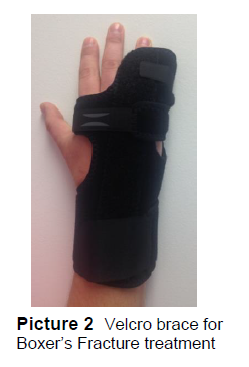

Der tages røntgenbilleder af hånden for at se, om der er tale om et brud. En boxerfraktur er en lillefingermetacarpalhalsfraktur (billede 1).